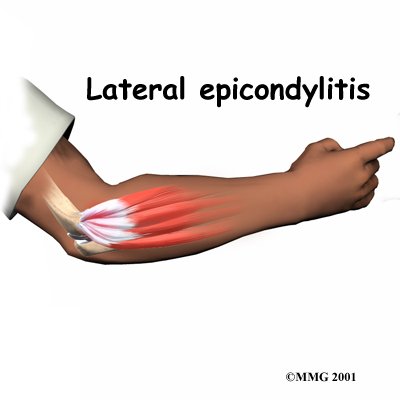

Lateral Epicondylitis -- Tennis Elbow

Lateral epicondylitis or tennis elbow is a painful overuse injury. It involves the inflammation or microscopic tearing of tendons that attach the forearm muscles to the outside of the elbow. Repetitive movements, such as swinging a tennis racquet, can cause this type of injury.